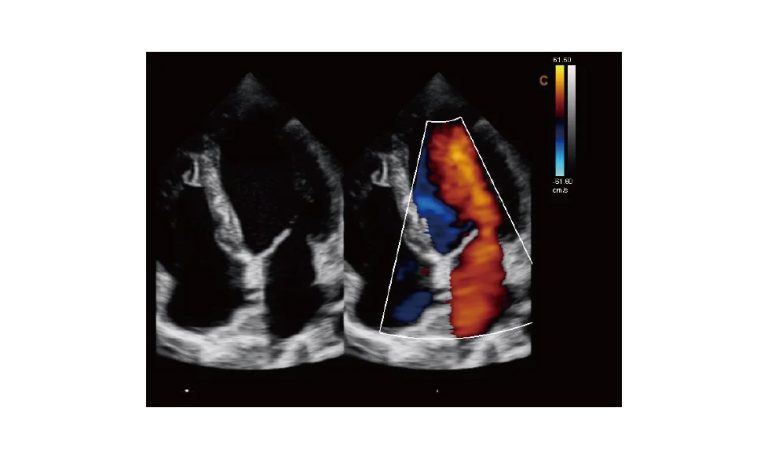

SonoScape Pro Pet E11

Smart Imaging

Introducing the first portable ultrasound with the C-Field+TM platform, redefining diagnostic imaging. Designed for veterinarians, it delivers unmatched clarity, ultra-fast processing, and seamless adaptability for all species. Experience Smart Imaging, Heartfelt Care—anywhere.

Equipped with cutting-edge veterinary software and optimized workflows, it embodies our commitment to Smart Imaging, Heartfelt Care – Wherever Their Journey Leads, with unparalleled performance and adaptability, this innovative system empowers veterinarians to provide exceptional care across all diagnostic applications,